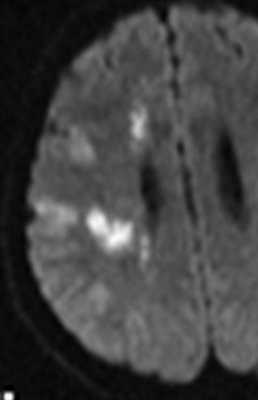

МРТ головного мозга. Диффузионно-взвешенная МРТ последовательность. ОНМК в острой стадии вследствие вазоспазма.